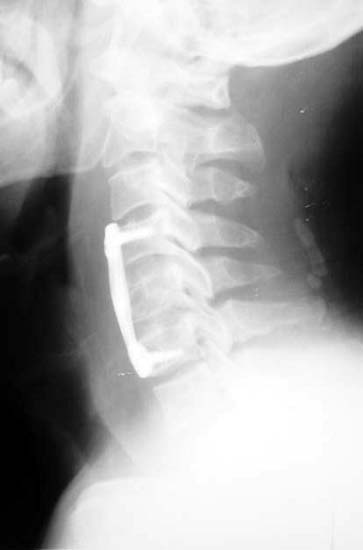

颈椎5骨折,椎体及间盘压迫硬膜囊,患者高位截瘫

前路减压,椎间植骨,钢板内固定,同期进行后路减压手术。 截瘫部分恢复,生活自理。